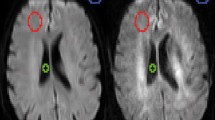

High-grade glioma patient. a post-contrast T1-weighted image; b post-contrast FLAIR image; c susceptibility-weighted image; d Diffusion coefficient map e DSC CBF map; f IVIM fD* map; g IVIM perfusion fraction map and h Map of diffusion kurtosis. The red arrow shows the tumor border in which there is BBB disruption. For the region pointed by the yellow arrow, there is no clear evidence of increased perfusion or BBB damage in DSC or post-contrast T1 images, but findings from the SWI, post-contrast FLAIR, and IVIM suggested high neovascularity and possible BBB damage. The pink arrow displays increased IVIM perfusion in the more infiltrative, edema-like, posterior regions

Figure 2 shows the images for patient 4 (Table 2) with a high-grade glioma. In this case, there is evidence of BBB disruption in the tumor borders (pointed by the red arrows), which is enhanced in the T1 post-contrast images (Fig. 2a). The same region also shows ITSS in SWI, indicating increased vascularization, also captured in DSC perfusion. In addition, IVIM f and fD* maps displayed increased values for these regions, suggesting sensitivity to BBB breakdown and neovascularity. Interestingly, in regions pointed by the yellow arrows, there is no clear evidence of BBB disruption according to T1 post-contrast images, but there are linear foci of increased f and fD* values, suggesting increased local perfusion and BBB damage, also captured in the post-contrast FLAIR. Of importance, it was also possible to capture increased IVIM perfusion fraction in the extensive areas of abnormal FLAIR signal around and posterior to the tumor (pink arrow), which was not detectable through DSC-CBF or SWI. The same areas also did not show any pathological enhancement on post-contrast T1. The analysis of the quantitative measurements for patient 4 in the boxplots of Fig. 3 shows that increase in perfusion-related parameters are more evident for IVIM outputs in comparison to DSC-CBF. The diffusion coefficient maps in Fig. 2d show increased diffusion in regions with increased perfusion and decreased diffusion in regions of high cellularity, according to the expected in the literature of diffusion imaging for tumors [27].

Boxplots of quantitative measurements for a Normalized DSC-CBF, and the IVIM output maps of b Diffusion coefficient, c fD* maps and d Perfusion fraction f for the ROIs of tumor border, tumor interior and edema of the HGG patient of Fig. 2. For fD* maps, the scale for regions of edema were higher than for Tumor border and interior, and therefore it was plotted in a secondary y axis in blue

Starting with HGG patients' analysis, the first finding is the increased IVIM perfusion in the tumor border (Fig. 2, red arrow). In this region, an enhanced signal in post-contrast T1-weighted images represents a viable hyperproliferative tumor whose increased demand for blood supply led to neovascularization and BBB breakdown. BBB disruption becomes evident by the extravasation of gadolinium from the intravascular compartment into tumoral tissues, perceived as areas of contrast enhancement [28]. In such regions, DSC-CBF was sensitive to increased perfusion, as well as IVIM maps, which agrees with previous studies [12, 14]. In that sense, increased perfusion fraction f maps reflected the increased blood content within the tumor even in regions with intact BBB function. Increased values in fD* maps suggest increased regional neovascularization, which is confirmed by analyses of susceptibility-weighted images that exhibit ITSS in the same regions of increased signal in IVIM perfusion-related maps. In the boxplots of Fig. 3, the perfusion fraction f was the most sensitive perfusion measurement to detect increase in blood flow in the tumor border, and both f and fD* maps showed higher vascularization in the tumor’s core.

Another interesting contribution of IVIM maps in HGG cases is the analysis of adjacent regions with abnormal T2 signals in FLAIR. For example, in patient 4, shown in Fig. 2, areas of hyperintensity in FLAIR extend over a large portion of the right hemisphere. Moreover, in the T2 hyperintense areas surrounding the necrotic lesion in Fig. 2b, there was also no evidence of BBB breakdown in post-contrast T1, nor of increased CBF in DSC maps or ITSS in SWI. However, IVIM f and fD* maps showed increased signal in those areas. In such cases, f and fD* maps could either be capturing subtle perfusional changes of underlying viable tissue or could be capturing remnants of edema, secondary to IVIM imperfect fitting. When planning surgical approaches in these cases, an important question lies in distinguishing areas that harbor viable neoplastic tissue that should be removed, responsible for future progression/recurrence, from areas representing just vasogenic edema. In this context, histopathological studies are necessary to investigate what tissue abnormalities underlie the increased perfusional fraction detected through IVIM on edema-like peritumoral regions. If viable tumoral tissue is detected in those regions, then IVIM probably offers an added value in delineating tumoral extent, outperforming other MRI techniques in detecting vascular changes that precede BBB leakage. In addition, among other HGG cases (supplementary material), foci of increased IVIM perfusion were found in regions of necrosis, which could also potentially represent remnant microvasculature and viable tumoral tissue [29].